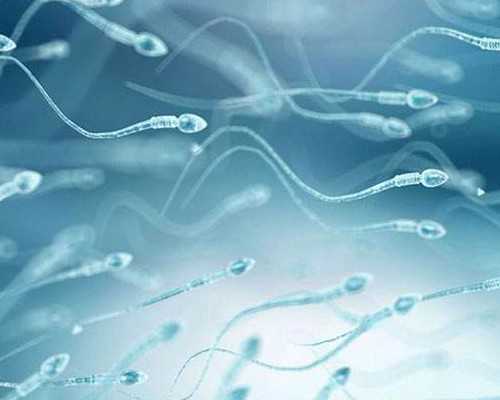

2、明確精液情況:檢查男方是否有足量、健康符合生育要求的精子,了解精子的數量和活動度等。如果精子正常,無需繼續檢查。如果精液質量異常,需要繼續查明原因,例如B超、性激素、染色體等,具體要根據醫生安排進行。